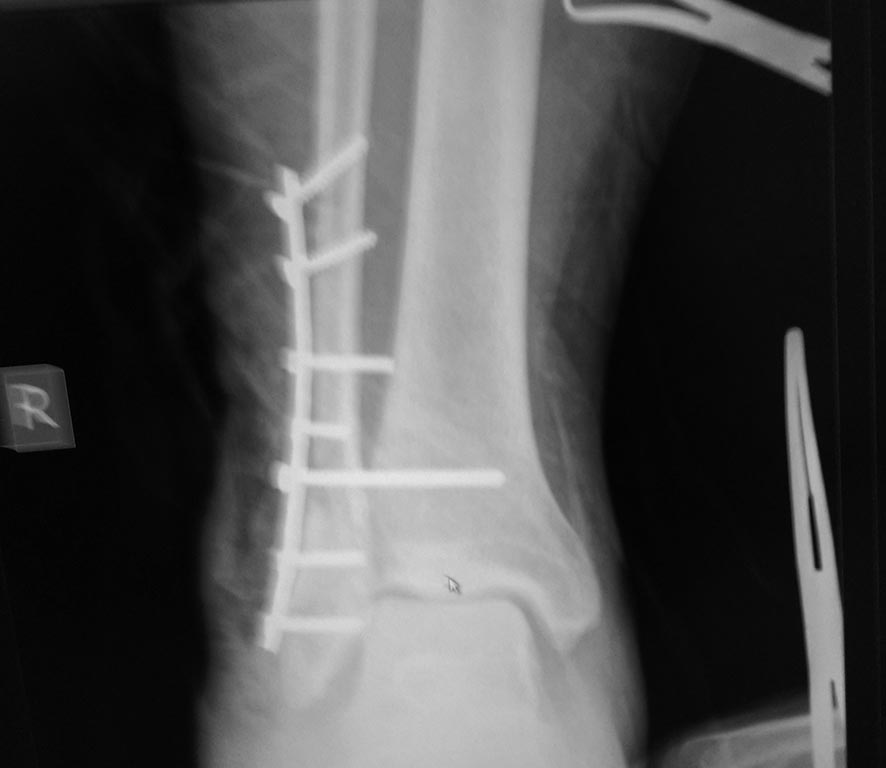

Здравствуйте. Выполнили остеосинтез несвежего перелома лодыжек с

подвывихом стопы. При интраоперационном рентгенконтроле подвывих

устранен. При контроле на следующий день - есть сомнения. Или это

особенности укладки?